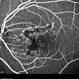

- macula serpiginous choroidopathy

- Tom Steele, CRA

TRC 50ex - Description

- 10/21/2009